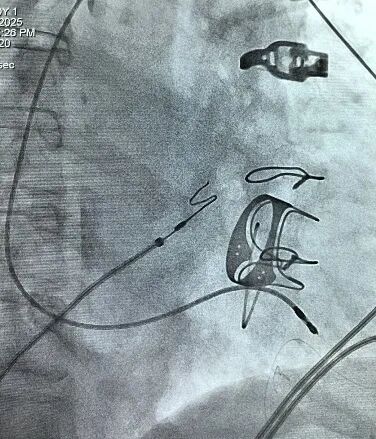

图3 手塑导丝3D间隔弯直接用普通心室螺旋电极行左束支起搏靶点图。可见左束支电位(P),P-V间期23ms;左室达峰时间86ms;起搏QRSd107ms;起搏阈值感知和阻抗分别为0.6V/0.4ms、

4mv和836Ω。走纸速度100mm/S.